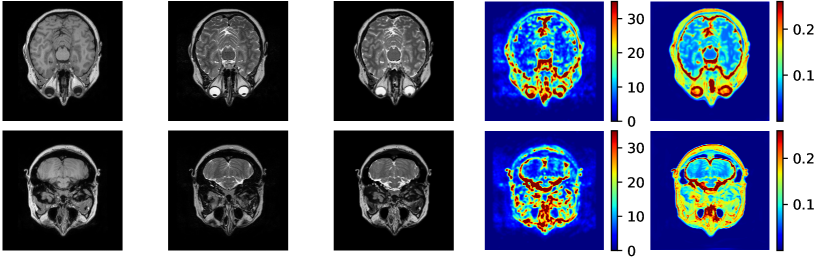

4.5 Uncertainty Scores

Additional to improved accuracy we demonstrate the efficacy of estimating the scale maps with the proposed method. The input-dependent non-negative scale maps are derived from the second output branch , see (9). Indeed, the predicted scale maps are able to model uncertainty inherent from data. This can be observed in Figure 8, where in addition to the transferred images also the predicted scale maps and the absolute residuals between predicted and ground truth images are displayed. Obviously, uncertainty is relatively greater in regions with higher residual values. From the scale maps it can be deduced for which positions the generator is comparatively uncertain in its prediction, such as the cerebral cortex and eye sockets in head MRI or the lateral knee ligaments in knee MRI.

[.44]

The correspondence between residual and scale maps suggests that the latter can be used as an approximation to a prediction’s residuals that are not available due to the lack of ground truth data in unsupervised learning. In order to quantitatively study this relationship we visualize mean absolute residual score and mean uncertainty maps for 512 randomly selected unseen test images in a scatter plot (see Figure 8). Moreover, we compare our uni-directional method UAPI also to the relations observed by UGAC that models uncertainty with the help of a bi-directional cycleGAN [9]. For modality propagation as well as accelerated MRI enhancement we visually observe an approximate positive linear correlation between mean absolute residual scores and mean uncertainty scores. We calculate the Pearson correlation coefficient (PCC) to obtain a quality estimate for the linear correlation and compare between UAPI and UGAC. Our method returns a slightly higher PCC on IXI (UAPI: 0.69, UGAC: 0.67). The discrepancy between both methods even increases on FastMRI (UAPI: 0.72, UGAC: 0.45). This further encourages the idea that scale maps derived from our approach can be used to indicate the overall quality of a transferred image.